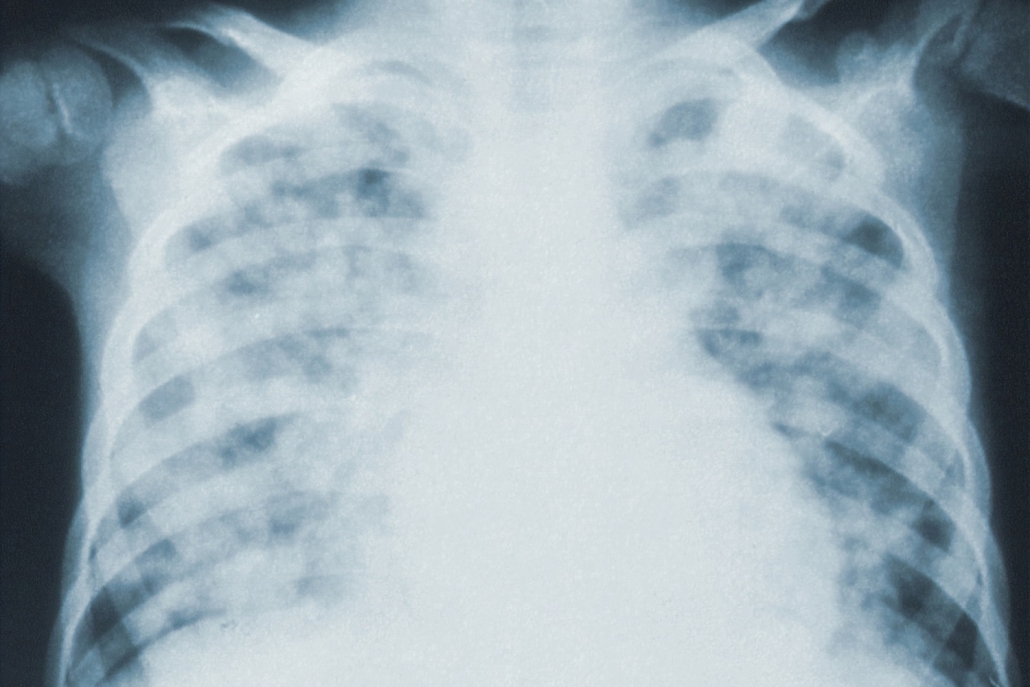

The ‘broken glass’ chest xray on the home page gives me pause. My son recently had an x-ray and now his doctor wants to reevaluate him for Covid19, Valley Fever (its Phoenix), and another ailment. Though most of his virus symptoms have cleared his breathing capacity is not returning. And he is young, a non-smoker, and works out several times a week, very fit. His first Covid19 test was negative, but he said the technician was fumbling in administering the swab and she and the Dr. seemed nervous. Perhaps their first such involvement.

Unfortunately, COVID-19 can do damage to the lungs. we don’t yet know if the damage will heal over time or if it’s permanent. This